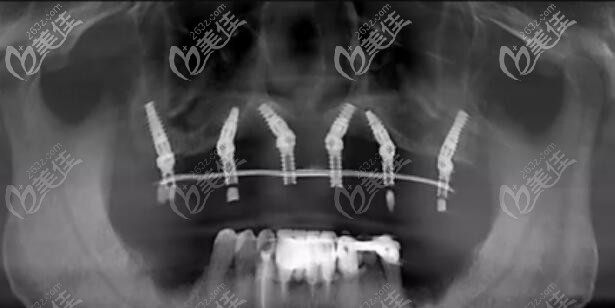

醫(yī)生介紹:北京平谷美銘口腔——劉亞忠主任:劉亞忠主任,從事口腔臨床工作數(shù)年,在牙周病、牙髓炎等口腔常規(guī)疾病的診斷和治療上積累了豐富的經(jīng)驗,也精通牙齒矯正和微創(chuàng)種植牙,以及種植正畸聯(lián)合治療。劉主任對待顧客親切和藹,能站在顧客立場上思考問題,結(jié)合顧客需求,為他們制定出個性化的治療方案。擅長項目——微創(chuàng)種植牙,牙齒矯正,綜合口腔修復(fù)。...